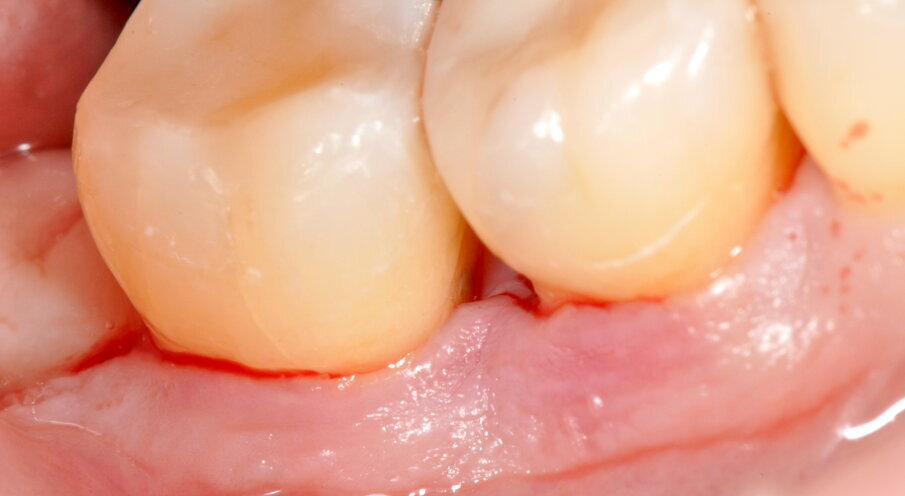

Si presenta alla nostra attenzione lamentando alitosi, mobilità e ipersensibilità dentale.

Viene perciò effettuata una visita parodontale completa con compilazione della cartella parodontale, set fotografico e raccolta dello status radiografico. Il profilo di rischio parodontale della paziente, stilato in base ai criteri del Periodontal Risk Assessment1 risulta essere di tipo “alto”. Vista la perdita di attacco clinico (CAL) nel sito con maggiore interessamento (≥5 mm), la perdita ossea valutata radiograficamente (RBL), la progressione della malattia (valutata “moderata”), la diagnosi è di Parodontite Generalizzata di Stadio IV e Grado B2. Osservando la cartella parodontale si può notare una maggiore progressione della malattia nei sestanti III, IV e VI con sondaggi superiori ai 6 mm a carico degli elementi 2.4, 3.6, 3.7, 4.4, 4.5, 4.6. e 4.7, BOP (Bleeding on Probing) positivo e SOP (Suppuration on Probing) positivo nei siti 2.4. e 4.6.

Fig. 1 - Fotografia frontale al T0.